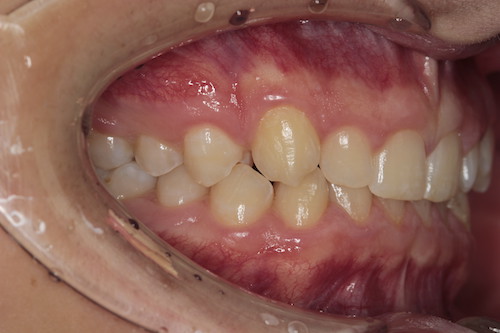

Частая ситуация, когда в общем все не плохо, но чего- то не хватает для идеала. Основной жалобой пациента было наличие выраженных промежутков на верхней челюсти, неровность положения зубов, глубокое перекрытие передних нижних резцов. Причина наличия промежутков заключалась в недостаточном размере по ширине боковых резцов верхней челюсти. именно поэтому после подъема высоты прикуса, нормализации наклонов зубов в переднем отделе, коррекции высоты перекрытия резцов, и доведение идеальных контактов в боковых отделах мы увеличили размер боковых резцов за счет композитного материала. Срок лечения 1 год.

До